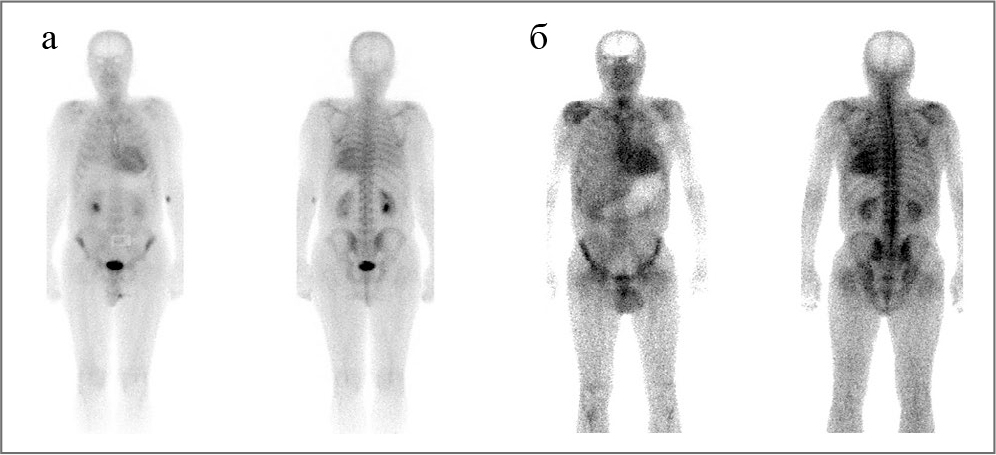

Согласно рекомендациям Европейского общества кардиологов (2014 г.) по ГКМП для пациентов, имеющих симптомы, признаки и неинвазивные маркеры амилоидоза, рекомендовано проведение остеосцинтиграфии (ОСГ) с биcфосфонатами.

ОСГ позволяет дифференцировать AL- и ТТ-амилоидоз по интенсивности поглощения миокардом РФП (99mTc-пирофосфат и 99mTc-DPD; класс IIа, уровень доказательности В) [12]. Более выраженный захват РФП наблюдается при ТТР-амилоидозе, более слабый – при AL-амилоидозе. Кроме того показано, что при неамилоидных формах кардиомиопатий захват РФП миокардом отсутствует [13–15].

Проведена статическая полипозиционная ОСГ с 99mTc-фосфотех (этидроновая кислота; «НПО Диамед», Москва) костей скелета в режиме «все тело» – очаги патологической фиксации РФП у пациента не выявлены. В проекции миокарда ЛЖ определяется среднеинтенсивное накопление РФП, что может свидетельствовать о наличии амилоидных отложений в миокарде (рис. 7, а).

Для сравнения приведены данные статической полипозиционной сцинтиграфии костей скелета в режиме «все тело» больного 60 лет с доказанным ATTR-амилоидозом, опубликованные нами ранее [16]. Индекс сердце/контрлатеральная область ˃1,5 характерен для транстиретинового амилоидоза, соответственно ˂1,5 – для AL-амилоидоза, что продемонстрировано на рис. 7.

Рис. 7. Результаты ОСГ пациента: изолированный кардиальный AL-амилоидоз (а) и при генетически обусловленном не-V30M-транстиретиновом амилоидозе (б); больной с AL-амилоидозом с преимущественным поражением сердца; а – коэффициент дифференциального накопления 1:1,43); б – больной с не-V30M ATTR с преимущественным поражением сердца. Коэффициент дифференциального накопления 1:1,99 [8, 9]